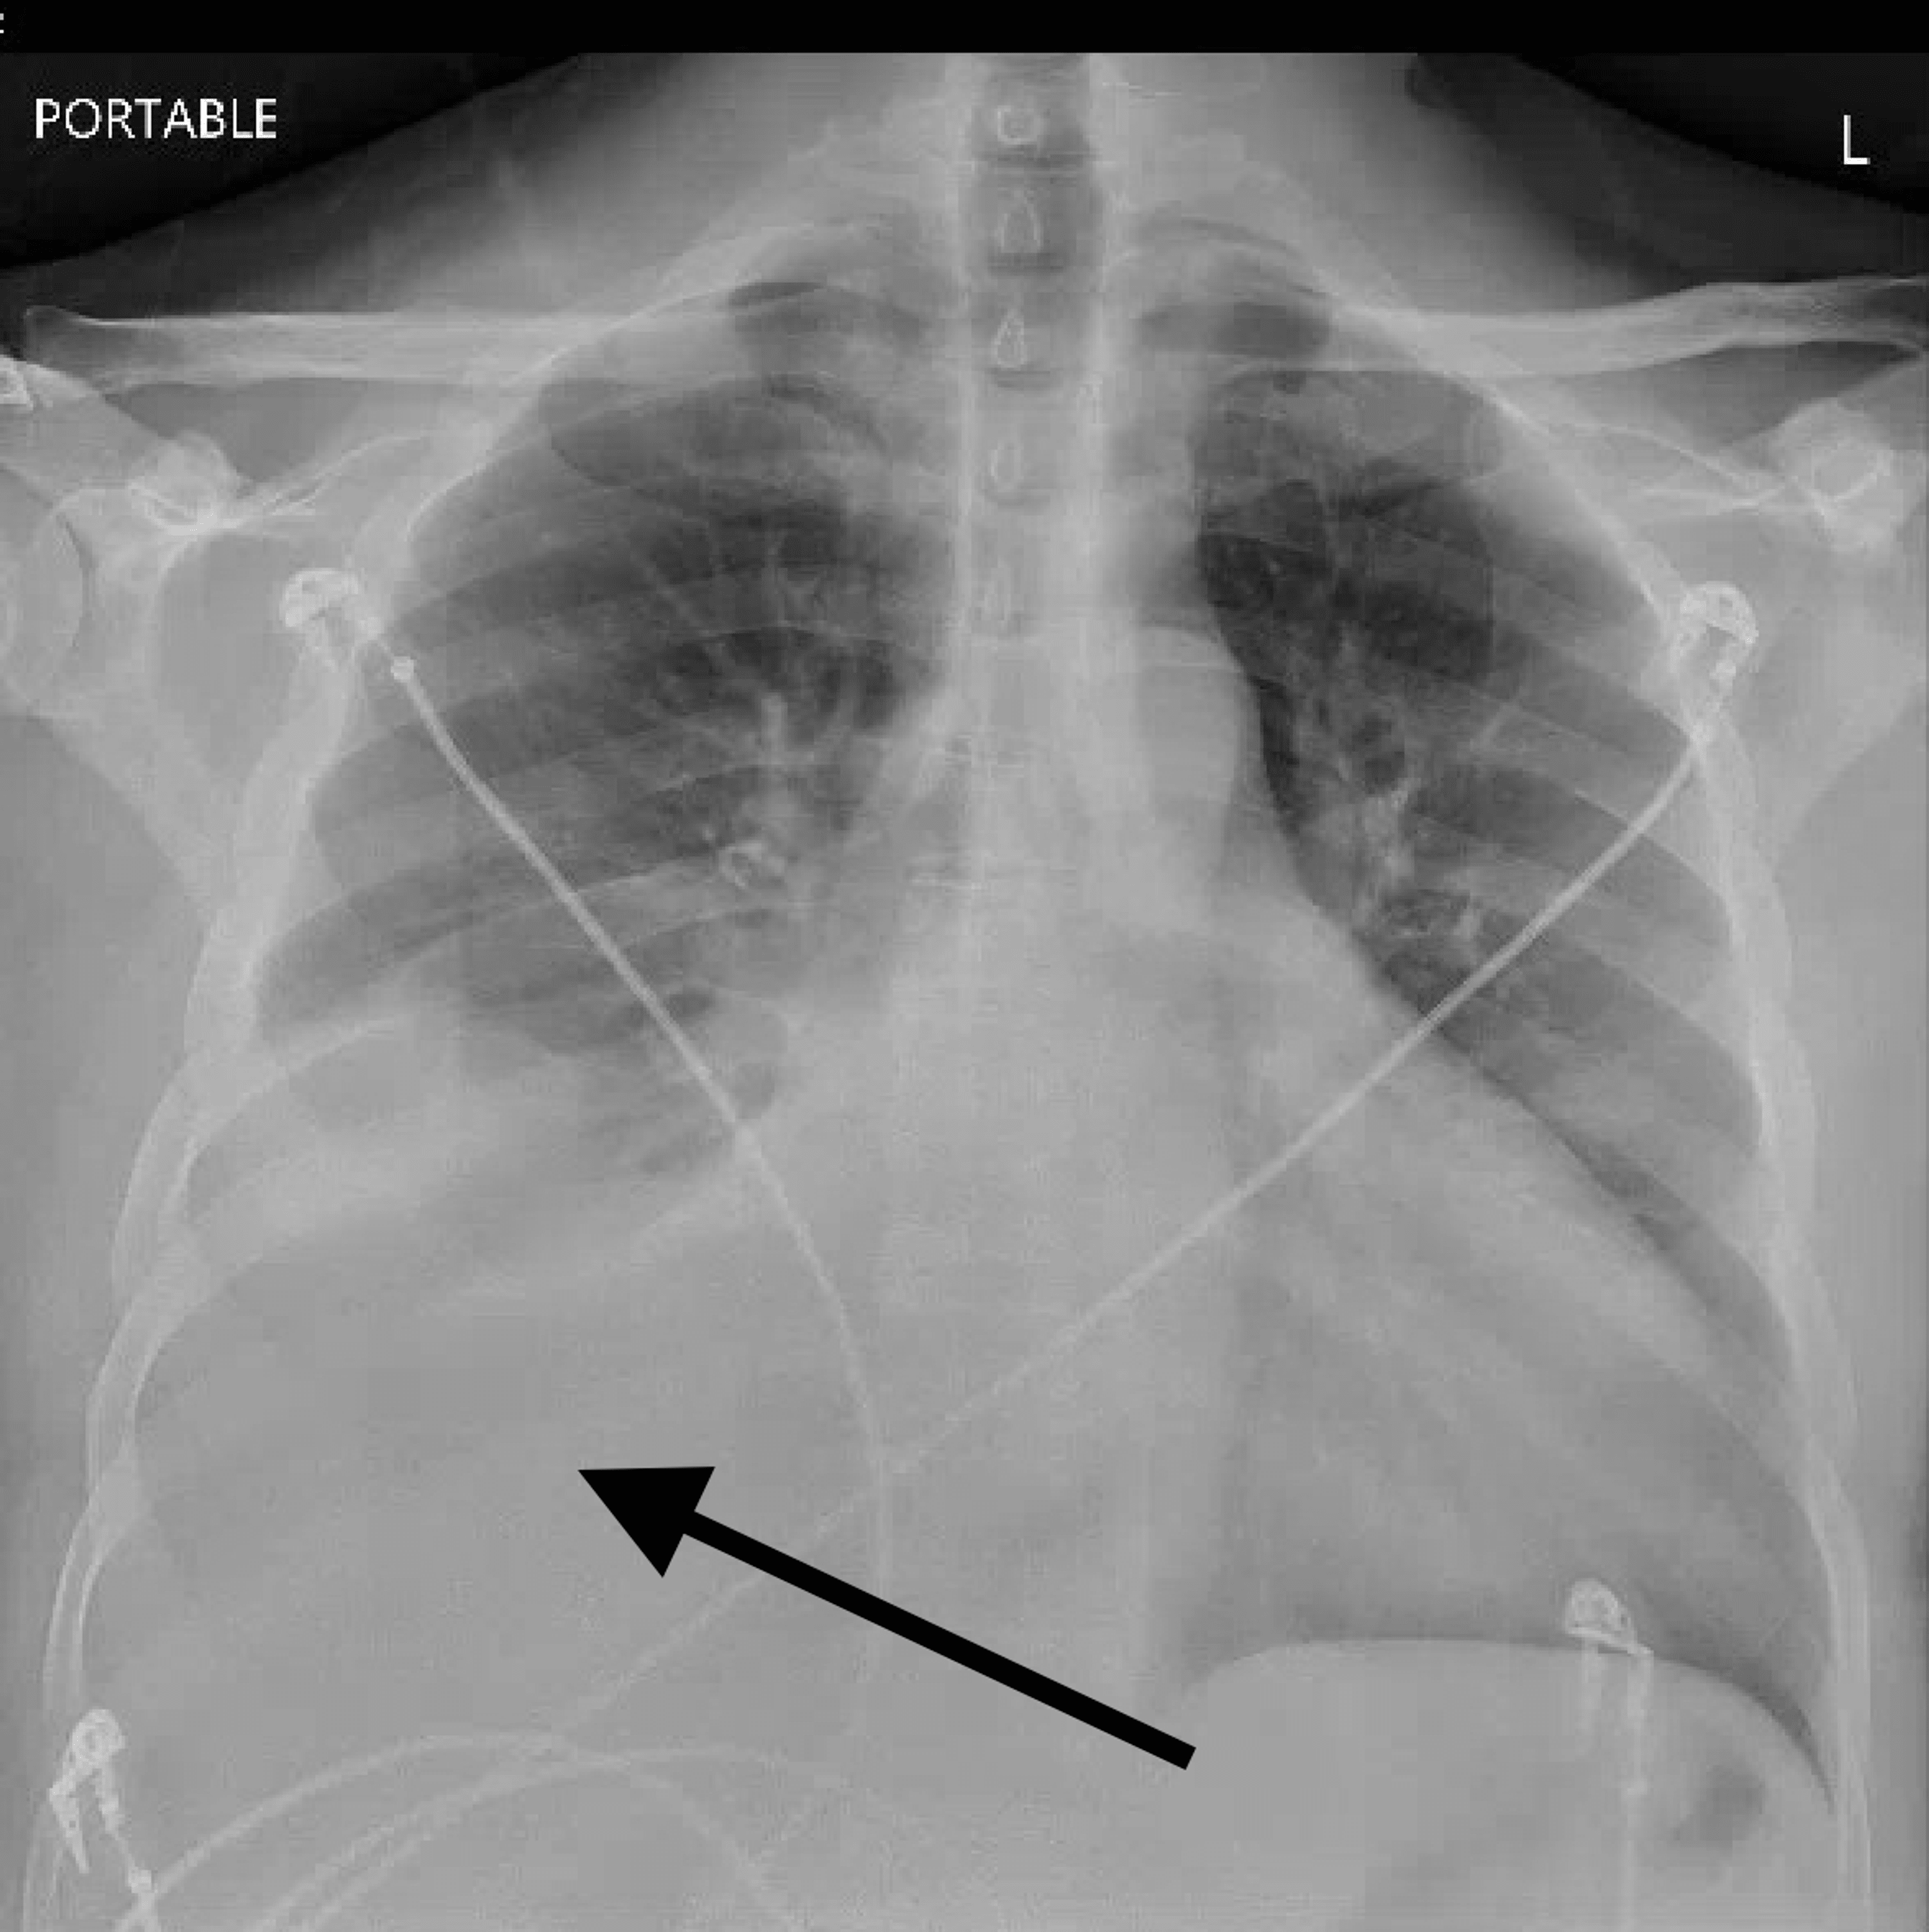

Chest X Ray Findings Heart Failure . Alveolar edema with perihilar consolidations and air bronchograms (yellow arrows); The following signs indicate heart failure: Heart failure is a growing public health problem and is now the most common cause of hospitalizations in the united states among patients.